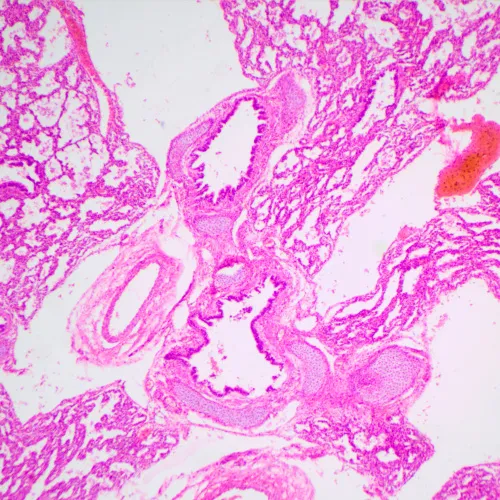

MAGUS Bio 240T eğitim ve araştırma amaçlı küçük bir biyolojik mikroskoptur. Aydınlık alan yönteminde biyolojik kaynaklı şeffaf ve yarı saydam numunelerle çalışmak üzere tasarlanmıştır. Mikroskop, her objektif için seçilen ışık yoğunluğunu koruyan kodlanmış, döner bir burun parçasına ve çalışma parametrelerini görüntüleyen bir LCD ekrana sahiptir.

• Aydınlık alan yönteminde şeffaf ve yarı saydam biyolojik numunelerle çalışır